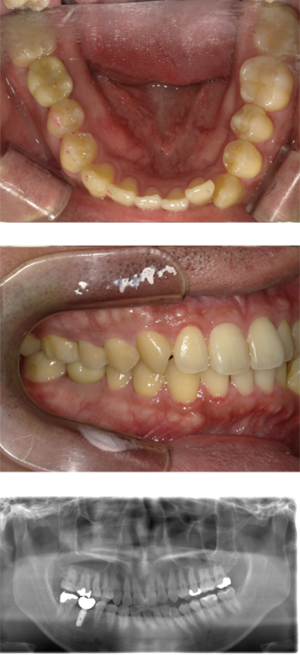

40代 女性 インプラント治療(右上64サイナス・GBR)

| 年代・性別 | 40代・女性 |

|---|---|

| 主訴 | 歯周病が進行し、抜歯適応となってしまったところにインプラント治療希望。 |

| 部位 | 右上⑥5④3② |

| 治療期間 | 約1年4ヶ月 |

| 費用 | ¥1,121,000(税込) |

| 副作用・リスク |

|